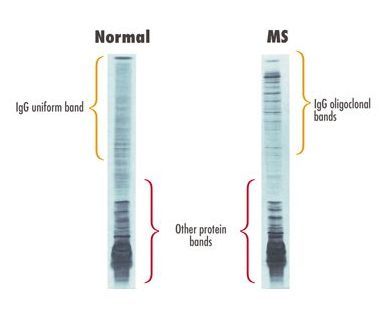

Oligoclonal Bands

- The presence of oligoclonal bands in the CSF that are not present in the serum indicates intrathecal IgG synthesis

- Nonspecific and can be seen in CNS infections and other CNS inflammatory conditions